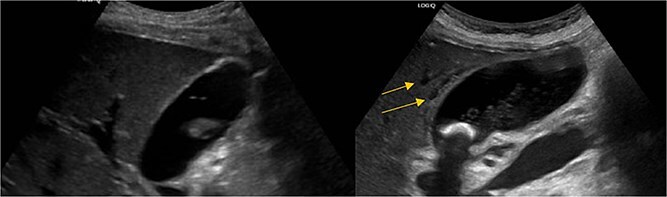

Stat CT scan showed new onset pericholecystic edema and hyperdense material within the common bile duct (CBD), not previously seen (Fig. 2). Stat Ultrasound confirmed findings of new onset acute cholecystitis (Fig. 3). Given the patient’s surgical history of gastric bypass, the decision was made to proceed with a robotic cholecystectomy with transcystic common bile duct exploration.